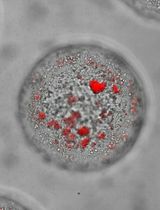

A Model of Breast Cancer Micrometastasis in a Three-Dimensional (3D) Liver Spheroid for Testing an Antimetastatic Therapy

Even though the survival and proliferation stages of cancer cells that have newly settled at a metastatic site are the rate-limiting stages and the most promising targets for drugs, there is a lack of models of the earliest stage of metastasis formation. A method for modeling breast cancer liver metastasis is described here: a stage of transition of a differentiated tumor cell into a cell actively proliferating in a three-dimensional (3D) liver spheroid. Opposite to existing heterocellular 3D models of metastases, the protocol allows modeling the initial stage of liver colonization by metastatic cells, the so-called “micrometastases.” The method includes obtaining a line of fluorescent tumor cells, fluorescence-activated sorting of differentiated cells, preparing a single-cell suspension of liver cells, forming a liver spheroid in an agarose mold, inducing the tumor cell dedifferentiation and proliferation using IL-6, and intravital microscopy of spheroids, with subsequent processing and analysis of fluorescent images in the ImageJ software. The performance of the proposed model was demonstrated using microRNA therapeutics. The ability of a combination of microRNAs to suppress the transition of micrometastasis to macrometastasis in the 3D liver spheroid was confirmed by an immunofluorescent assay of spheroid sections and transcriptome analysis.